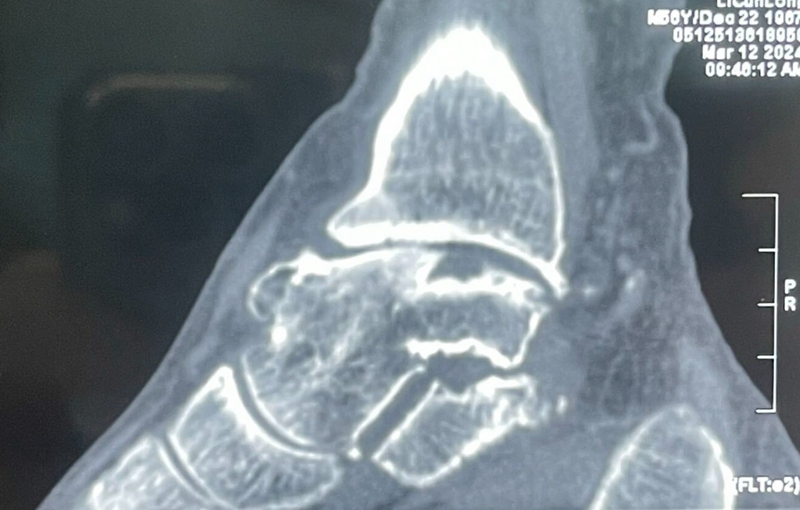

23 手术后资料